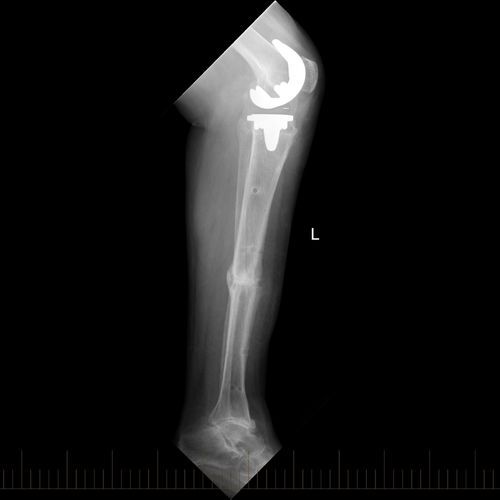

Adult with Correction of the Lower Limb Deformity due to Rickets